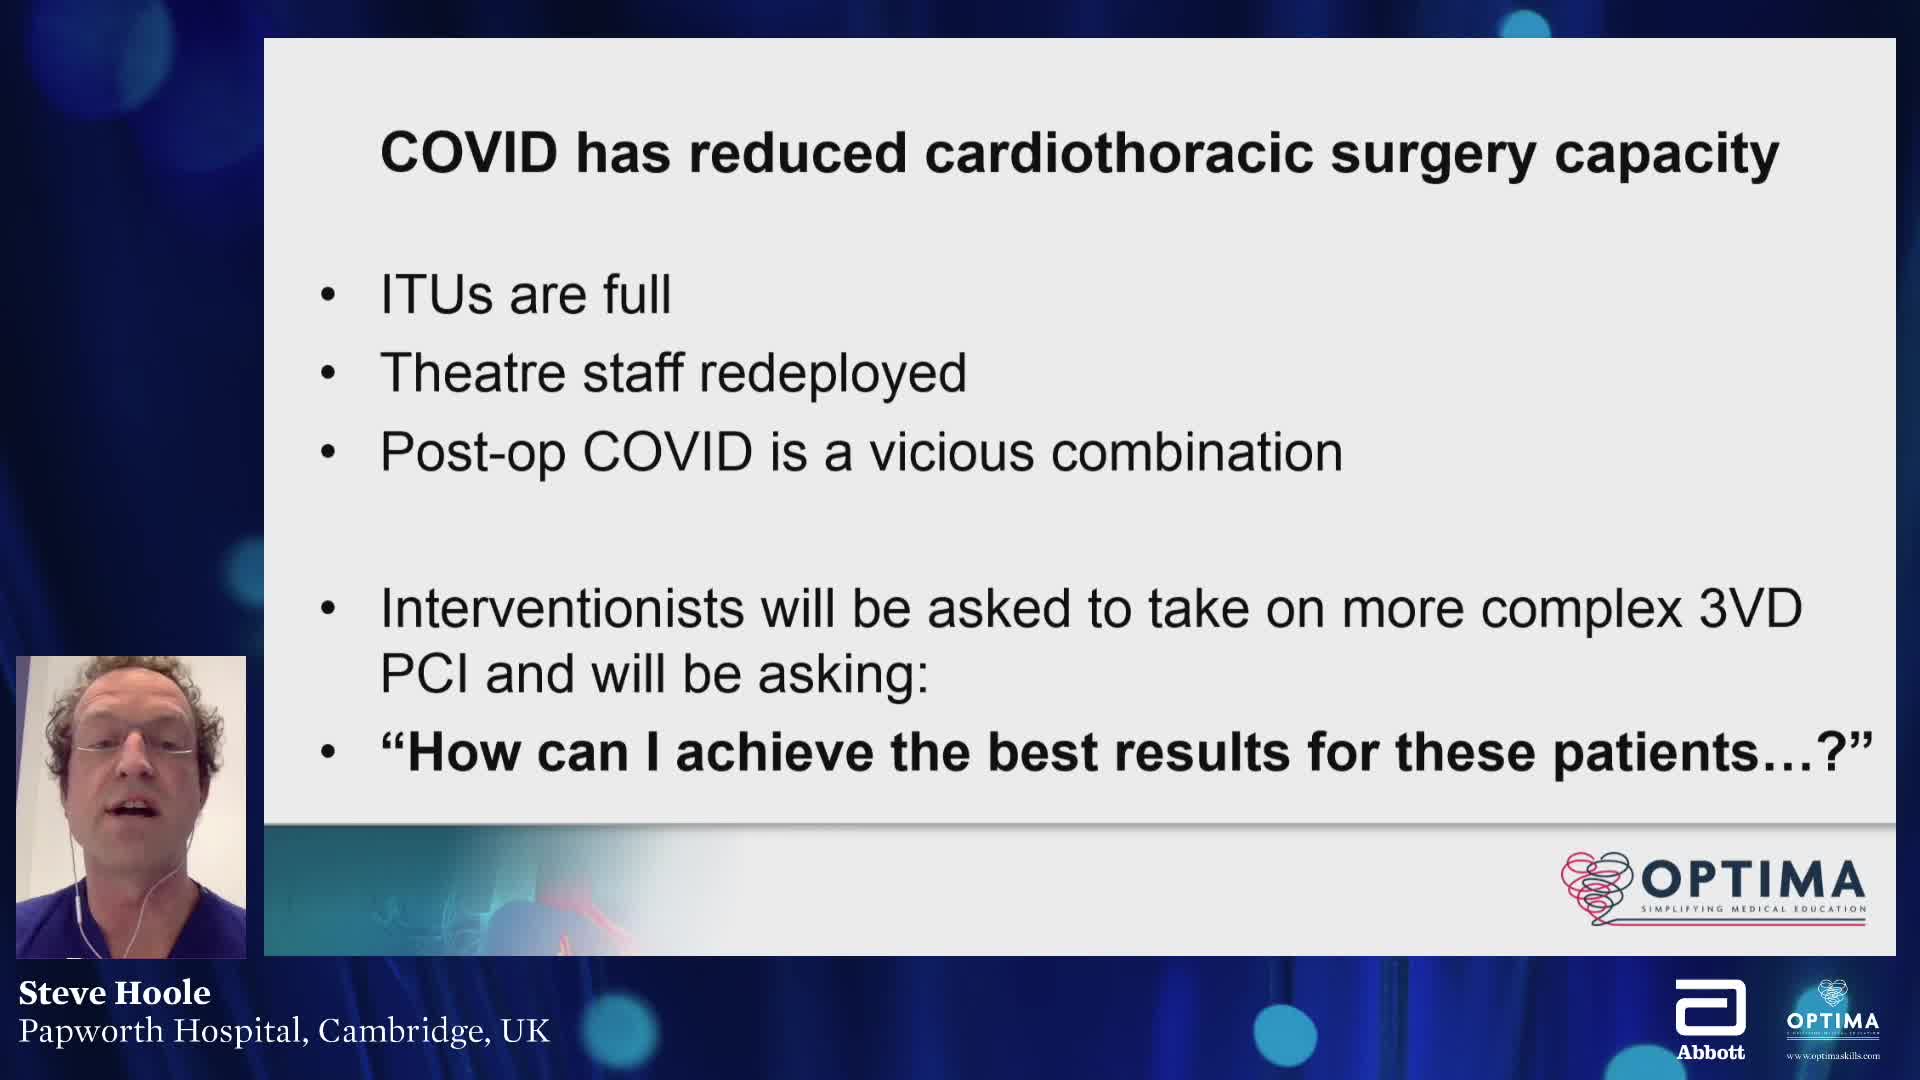

Past Courses: CORE Webinars Edition 1: COVID-19 era: Managing surgical downturn patients in the cathlab.